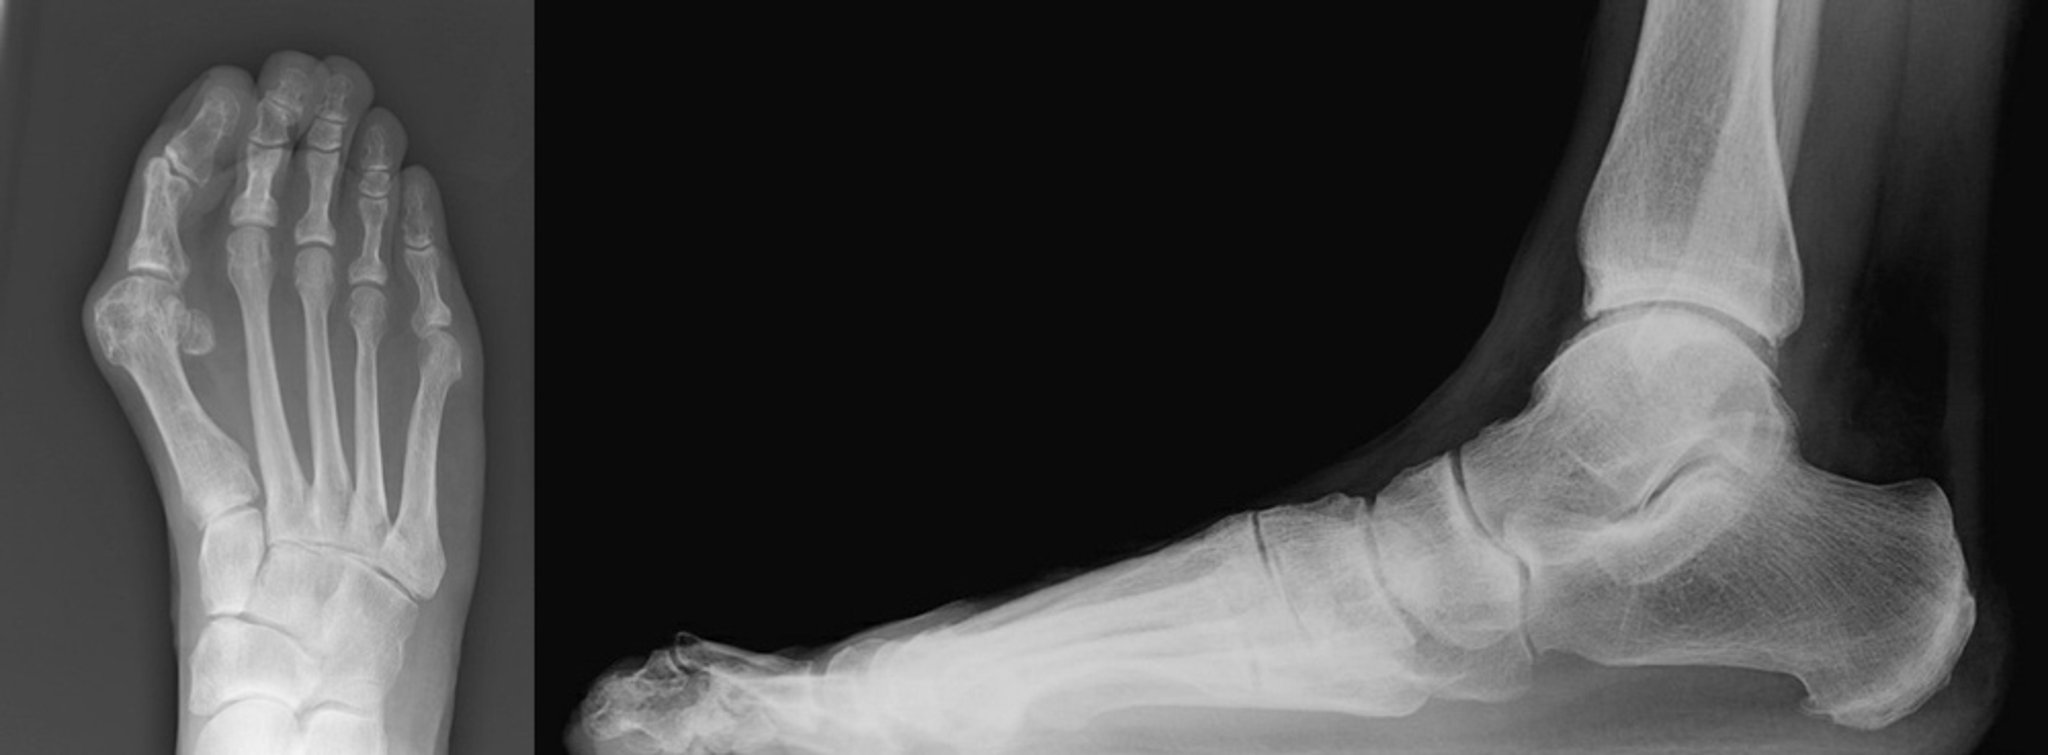

Bunion with Hammertoe Radiographs

Anteroposterior and lateral views of a bunion with a hammertoe of the second toe are shown.

The anteroposterior view shows severe hallux valgus with medial deviation of the first metatarsal bone. There is abutment of the hallux to the second toe. The second digit is deviated laterally with narrowing of the second metatarsophalangeal joint (left).

The lateral view shows the second toe is dislocated at the metatarsophalangeal joint. There is hyperflexion at the proximal interphalangeal joint with hyperextension of the distal interphalangeal joint of the second toe (right).

Images courtesy of James C. Connors, DPM.